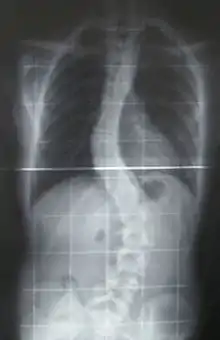

Scoliosis (pl.: scolioses) is a condition in which a person's spine has an abnormal curve.[2] The curve is usually S- or C-shaped over three dimensions.[2][7] In some, the degree of curve is stable, while in others, it increases over time.[3] Mild scoliosis does not typically cause problems, but more severe cases can affect breathing and movement.[3][8] Pain is usually present in adults, and can worsen with age.[9] As the condition progresses, it may impact a person's life and hence, can also be considered a disability.[10]

When scoliosis is suspected, weight-bearing, full-spine AP/coronal (front-back view) and lateral/sagittal (side view) X-rays are usually taken to assess the scoliosis curves and the kyphosis and lordosis, as these can also be affected in individuals with scoliosis. Full-length standing spine X-rays are the standard method for evaluating the severity and progression of scoliosis, and whether it is congenital or idiopathic in nature. In growing individuals, serial radiographs are obtained at 3- to 12-month intervals to follow curve progression, and, in some instances, MRI investigation is warranted to look at the spinal cord.[79] An average scoliosis patient has been in contact with around 50–300 mGy of radiation due to these radiographs during this time period.[80]

The standard method for assessing the curvature quantitatively is measuring the Cobb angle, which is the angle between two lines, drawn perpendicular to the upper endplate of the uppermost vertebra involved and the lower endplate of the lowest vertebra involved. For people with two curves, Cobb angles are followed for both curves. In some people, lateral-bending X-rays are obtained to assess the flexibility of the curves or the primary and compensatory curves.

Scoliosis is defined as a three-dimensional deviation in the axis of a person's spine.[45][7] Most instances, including the Scoliosis Research Society, define scoliosis as a Cobb angle of more than 10° to the right or left as the examiner faces the person, i.e. in the coronal plane.[85]